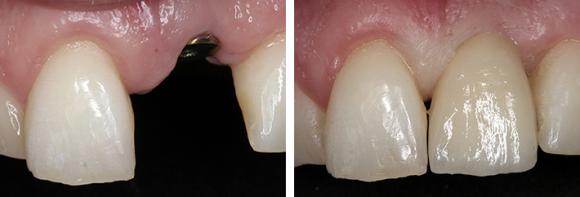

Implantti on leukaluuhun kiinnitettävä, yleensä titaanista valmistettu keinojuuri. Se kiinnittyy ympäröivään leukaluuhun muutamassa kuukaudessa. Implantteihin voi kiinnittää esimerkiksi kruunuja, siltoja tai irtoproteeseja.

Implanteilla voidaan korvata proteettisesti yksi hammas tai useita hampaita. Myös hampaattoman leuan kokoproteesi voidaan korvata implanttisillalla, tai proteesi voidaan kiinnittää implanttijuuriin.

- Paranemisvaiheen jälkeen aloitetaan kruunun, hammassillan tai irrotettavan proteesin valmistus ottamalla tarvittavat jäljennökset. Proteesin valmistus vaatii yleensä muutaman hoitokäynnin.